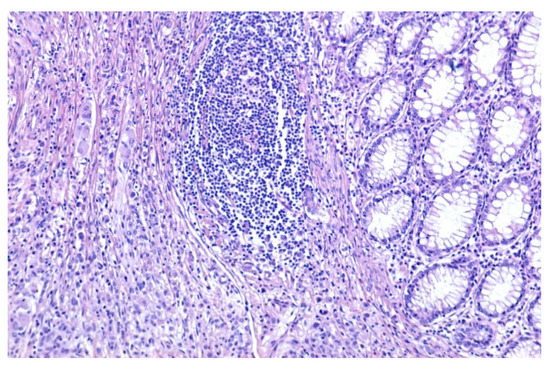

The histopathological diagnostic of the postoperator specimen (4394) was colonic malakoplakia as illustrated in Figure 2 and Figure 3.

Figure 3.

Dense macrophage infiltrate with rare dispersed lymphocytes (HE, ×200).

The microscopic examination revealed:

- a significant architectural remodeling of the colonic mucosa and submucosa with dense cellular inflammatory infiltrate,

- the dense cellular inflammatory infiltrate-composed of epithelioid macrophages with wide eosinophilic cytoplasm, variable-sized nuclei, with occasional nucleoli,

- dispersed syncytia with the appearance of multinucleated giant cells, with chaotically disposed nuclei and

- amorphous cytoplasmatic inclusions of cellular detritus type, with sporadic intercalated lymphocytes.

Neither areas of necrosis, nor viable microorganisms were detected.